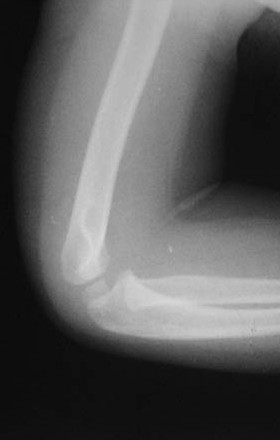

男儿,5岁,左肘部外伤,局部肿胀一天。

左肱骨小头上方骨皮质不连续,隐示一';线';型骨折线,软组织肿胀,考虑左肱骨小头骨骺分离

左肱骨小头[肱骨小头位于前线之前,9岁以下应该位于前线之后]上方骨皮质不连续,隐示一';线';型骨折线,软组织肿胀,考虑左肱骨小头骨骺分离。

左肱骨小头骨骺干骺端骨折。

[quote]以下是引用wk8888在2006-5-22 19:48:00的发言:[br]左肱骨小头上方骨皮质不连续,隐示一';线';型骨折线,软组织肿胀,考虑左肱骨小头干骺端青枝骨折

表现:正位肱骨远侧干骺端可见横行低密度线延伸至外髁,外髁皮质断裂,侧位前侧骨皮质也有断裂。对侧好像有类似之处,但那是与肱骨小头骨骺的重叠影。

印象:肱骨低位髁上骨折